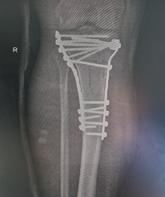

Schatzker III, Osteosinteză cu șuruburi percutană

Schatzker VI, Reducere sângerândă și osteosinteză cu 2 plăci

În fracturile Schatzker I, fără leziuni de menisc extern asociate este indicată reducerea și osteosinteza percutană cu șuruburi. Dacă leziunea de menisc este evidențiată pe RMN, se poate opta pentru reducere și osteosinteză percutană cu șuruburi asociată cu artroscopie(12), având rol de control al reducerii și curativ pentru leziunea de menisc, sau reducere deschisă și fixare internă cu placă și șuruburi.

La pacienții tineri cu fracturi Schatzker tip II și III se poate opta pentru reducere și osteosinteză percutană cu șuruburi asociată cu artroscopie. O altă variantă este cu grefă osoasă și reducere deschisă cu fixare internă cu placă și șuruburi. Controlul reducerii intraoperator se realizează artroscopic sau cu C arm.